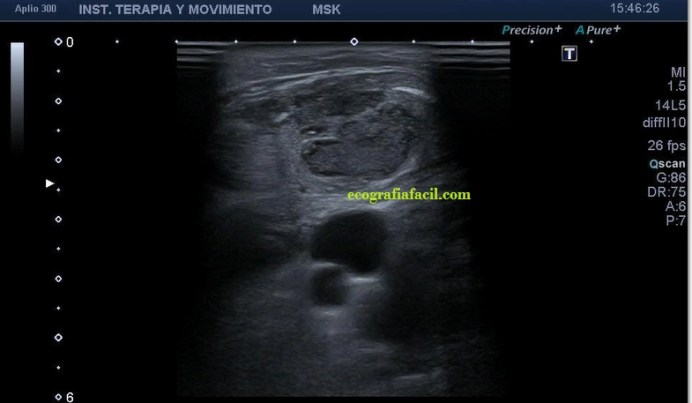

La ecografía muscular realizada evidencia una pérdida del patrón muscular normal en

el esternocleidomastoideo, con engrosamiento del mismo y semiología heterogénea en su tercio distal. Hay ganglios locorregionales hipoecogénicos con un patrón claramente reactivo aunque mantienen su tamaño subcentimétrico (Imagen 5).

A la altura de la bifurcación carotídea (imagen 6) el ECM adopta una apariencia más normal, su semiología es la típica del músculo. hipoecogénico y homogéneo, con ese patrón normal de «cielo estrellado» en eje corto como dice, mi querido amigo en sus clases, el Prof. Javier Álvarez, que tan amablemente me ha cedido estas imágenes para compartirlas en el Blog.

Desde la imagen 1 hasta la 4 realizadas en eje corto, el ECM está afectado claramente, pero en la imagen 7 donde ves un corte en eje largo puedes observar como el tejido celular subcutáneo también ha cambiado su aspecto y no es hipoecogénico, sino que es ligeramente hiperecogénico y que corresponde en cercanía con la afectación infecciosa del músculo, ojo a todos lo detalles (ganglios incluidos), que el árbol no nos impida ver el bosque…